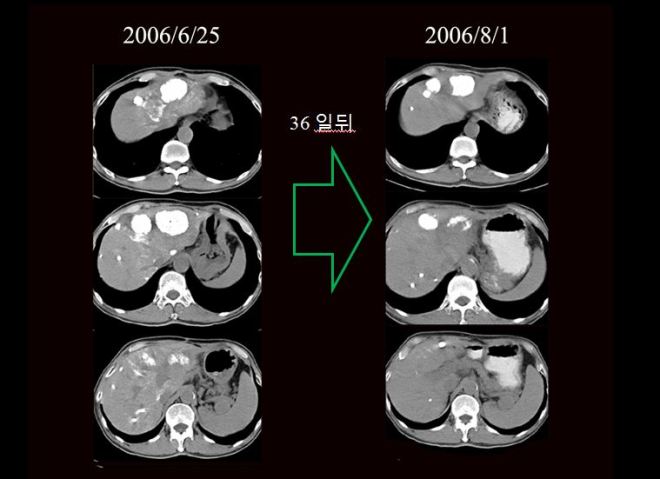

위에서 보듯이 간우엽에 보이던 large mass가 대충 어림잡아도 길이로 2배가 색전술 뒤에 커졌으니 체적으로 따져 본다면 2x2x2 =8 로 적어도 색전술 이후에 40일만에 체적대비 8배로 종양이 커졌다. 또한 아래에서 보듯이 우측에 흉수가 급격히 차오르는 결과가 나타났다.

다음은 색전술 1년 뒤인 2005년도 CT 사진이다.

간에 있던 암들이 현저히 소실이 되어서 암이 보이는 부분만 수록하였으므로 위와 level이 조금 다르다. 하지만 이전에 보이던 간 좌엽의 우들두들하던 경계면의 간이 약간 재생되어서 자라면서 매끈해졌고 리피오돌 uptake 된 부분이 현저히 줄어들었다. 다음은 2004년과 약 8개월 뒤인 2005년도의 비교 사진이다. 우리는 두 사진을 비교해 볼 때 색전술이 매우 잘 반응을 했음을 알 수 있다.

이후 내원 당시 2006년도 사진과 비교해 보겠다.

이 사진을 비교해 보면 level들이 약간씩 다르지만 가장 중점적으로 암이 보이는 부분을 담았다. 아래쪽사진에서는 2005년 10월보다 2006년 5월이 다소 더 증가한 듯이 보인다. 하지만 main인 위쪽 사진은 많이 종양이 감소되었고 2004년도와 비교해 보면 간 좌엽은 경화로 보이던 면도 매우 매끄러워져 있어서 간경화도 소실된 분위기이고 암도 잘 멈추어 있다고 볼 수 있다.